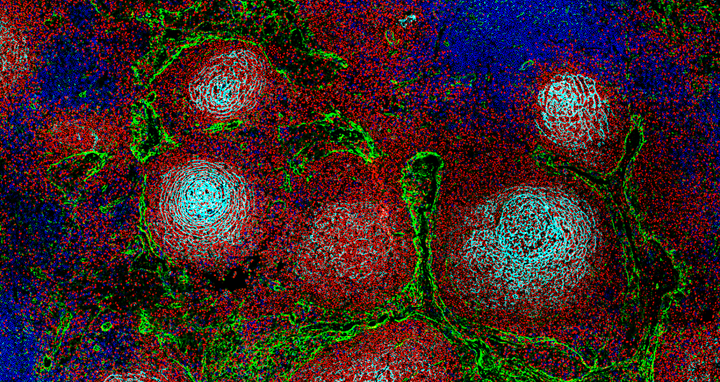

Structure of a lymph node showing the typical division into different territories for immune cells: B cells are shown in red, T cells in blue, lymphatic vessels in yellow, and stromal cells in cyan.

Structure of a lymph node showing the typical division into different territories for immune cells: B cells are shown in red, T cells in blue, lymphatic vessels in yellow, and stromal cells in cyan. Photo: Marc-Andrea Bärtsch, Felix Czernilofsky, Med‑V UKHD